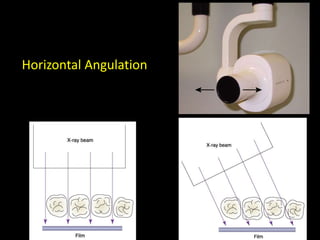

2. The paralleling cone technique provides accurate images with little magnification and no superimposition but is more difficult for patients. The bisecting angle technique is easier for patients but results in more image distortion.